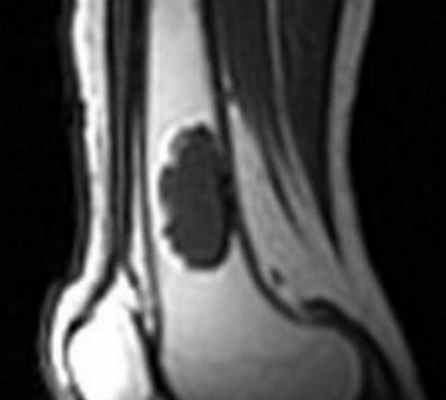

Особенность неоссифицирующей фибромы является ее кортикальная локализация при рентгенографии или МРТ коленного сустава. Опухоль доброкачественная, типична для молодого возраста. При МРТ коленного сустава имеет темную зону склероза, хорошо контрастируется по солидному типу. Фиброзный корткальный дефект при МРТ коленного сустава не контрастируется.

• Чувствительные к жидкости МР-последовательности: неоднородный характер-зоны гипо- и гиперинтенсивного сигнала:

о 80% случаев: по крайней мере в части поражения имеется гипоинтесивный сигнал

о В большинстве случаев на Т2 ВИ визуализируются перегородки

о Высокоинтенсивное контрастное усиление периферии поражения и перегородок; степень контрастирования центральных отделов поражения зависит от степени склероза

Неоссифицирующая фиброма (фиброзный кортикальный дефект, фиброксантома) представляет собой доброкачественный фиброзный дефект кости, который на рентгенограмме выглядит как четко очерченная зона повышенной прозрачности. Очень маленькую неоссифицирующую фиброму обозначают как фиброзный кортикальный дефект. Эти изменения представляют собой дефекты развития, в которых часть кости, подвергающаяся в норме оссификации, заполняется фиброзной тканью. Обычно они возникают в области метафизов, особенно часто в дистальном отделе бедра, в дистальном и проксимальном отделах большеберцовой кости. Неоссифицирующие фибромы часто встречаются у детей. В большинстве случаев изменения в итоге оссифицируются и подвергаются ремоделированию, часто с формированием плотных склеротических зон. Тем не менее, некоторые дефекты увеличиваются. Часто являются случайными находками при рентгенологическом исследовании.